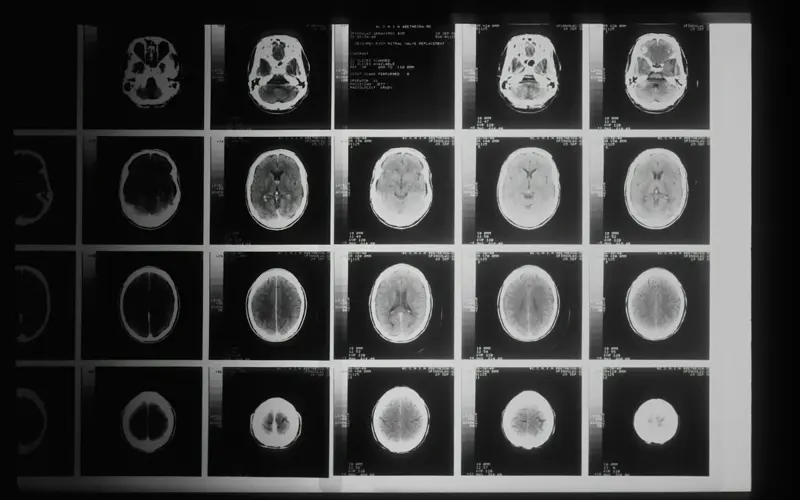

x-ray image of a rib cage

iCAIRD

Lead organisations: NHS Greater Glasgow and Clyde, the West of Scotland Innovation Hub, Canon Medical Research Europe

Read the case study